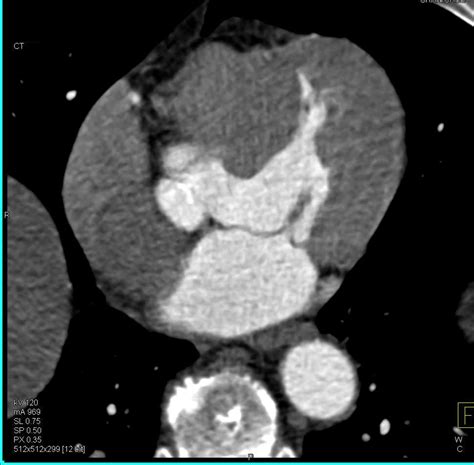

Hypertrophy Left Ventricle With Thickened Wall - Chest Case Studies

Hypertrophy Left Ventricle with Thickened Wall - Chest Case Studies www.ctisus.com

hypertrophy ctisus ventricle

Lymph mediastinum mediastinal nodes radiology hilar radiologyassistant radiographics istant. Liver ct cancer colon ctisus case metastases diagnosis studies. Hypertrophy left ventricle with thickened wall